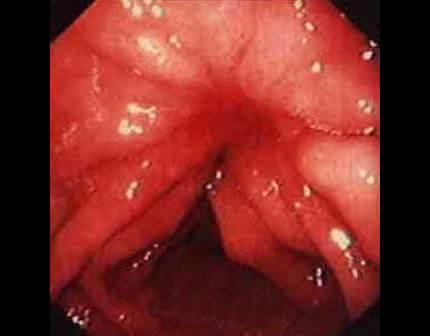

摘要:痔瘡癌變是嚴(yán)重的健康問(wèn)題,其前兆包括便血、疼痛、肛門(mén)不適、排便習(xí)慣改變等10個(gè)跡象。了解并識(shí)別這些前兆的重要性在于早期發(fā)現(xiàn)、診斷和治療,以提高治愈率和生存率。對(duì)于痔瘡患者,密切觀察并及時(shí)就診是預(yù)防癌變的關(guān)鍵。

痔瘡癌變的10個(gè)前兆

1、痔瘡疼痛加?。褐摊徎颊呷绺杏X(jué)疼痛逐漸加劇,可能是癌變的一個(gè)信號(hào)。

2、痔瘡出血:長(zhǎng)期痔瘡出血,尤其是出現(xiàn)持續(xù)性出血時(shí),應(yīng)警惕癌變的可能。

3、痔瘡體積變化:如痔瘡體積在短時(shí)間內(nèi)迅速增大,可能是癌變的征兆。

4、排便習(xí)慣改變:如排便頻率增加或減少,以及出現(xiàn)便秘與腹瀉交替的情況,可能與痔瘡癌變有關(guān)。

5、肛門(mén)不適:出現(xiàn)肛門(mén)墜脹、異物感等癥狀時(shí),應(yīng)考慮痔瘡癌變的可能性。

10、便血顏色變化:如便血顏色由鮮紅色變?yōu)榘导t色或混合有黏液,應(yīng)引起重視。